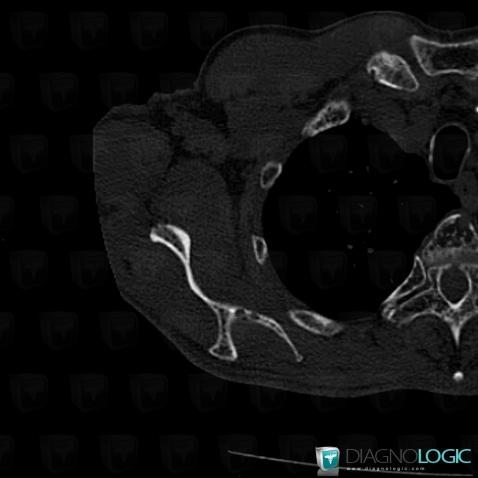

Multiple myeloma, Ribs, CT

Here is the specific information in the key image above:

- Diagnosis Multiple myeloma, Location(s) Ribs, with gamuts Osteolytic lesion of ribs